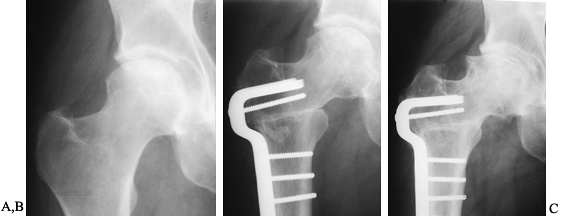

(stages I to IV-B) (Fig. 125.19). This

Figure 125.19. Radiographs of the left hip of an active young man with alcohol-related avascular necrosis. A: Preoperative radiographs show a large area of sclerosis and radiolucency within the femoral head. B:

Radiographs taken 1 year following core decompression and bone grafting show that the lucent areas have begun to fill in with bone. The patient remained essentially asymptomatic and was clinically doing well 12 years after the surgery. |